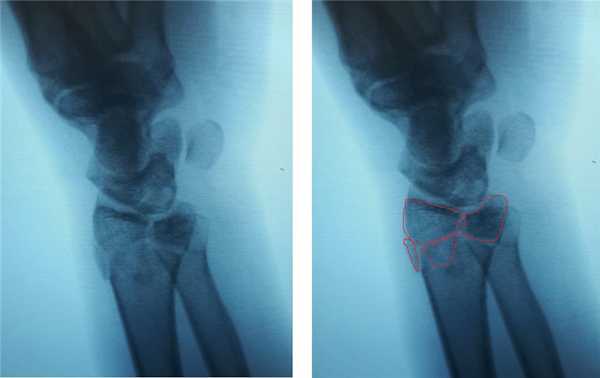

Внешний вид конечности после снятия гипсовой повязки. Рентгенограммы выполненные при помощи ЭОП на операционном столе выявили полное смещение всего дистального метафиза лучевой кости к тылу на целый поперечник.

Когда имеешь дело с таким переломом на фоне остеопороза становится ясно, что в метафизарной зоне будет «каша» из множества мелких отломков, и что суставная поверхность будет расколота минимум на 3 части.

После репозиции на рентгенограммах отчётливо виден многоооскольчатый, нестабильный характер перелома.

Окончательный остеосинтез после проведения всех винтов выглядит на рентгенограмме примерно так. На левой части рисунка схематично отображено расположение фрагментов кости, фиксированных пластиной.